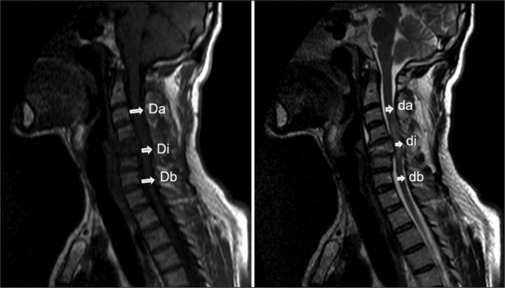

Results: The incidence of SCI was 98.7 per million. The median age was 37 years (IQR: 27-52), with 86.4% of the patients being male. Common causes included diving into shallow water (30.5%) and falling from heights (25.4%). Complete injury (ASIA A) was observed in 40.7% of cases, while incomplete injury (ASIA B, C, D, and E) was found in 59.3%. The most frequently affected levels were C4 (18.6%) and C5 (23.7%). No improvement was observed in the complete injury group, whereas 44% of the incomplete injury group showed improvement (P < 0.001). Common MRI findings included cord edema (96.6%), vertebral fracture/dislocation (86.4%), and soft-tissue injury (84.7%). Significant differences in MRI findings between the complete and incomplete SCI groups were observed in vertebral fracture/dislocation (P = 0.016), cord compression (P = 0.003), canal stenosis (P = 0.008), intramedullary hemorrhage (P ≤ 0.001), hemorrhage/hemorrhagic contusion (P ≤ 0.001), anterior ligament damage (P = 0.001), posterior ligament damage (P = 0.01), maximum canal compression (MCC) (P = 0.006), and lesion length (P = 0.008).

Conclusion: Traumatic SCI primarily affects young males, often resulting from activities such as diving into shallow water, falls from heights, and motor vehicle accidents. Initial clinical assessments are insufficient for predicting neurological outcomes. Although MRI findings are more frequent in complete SCI, lesion length, and MCC do not reliably predict short-term neurological improvement.